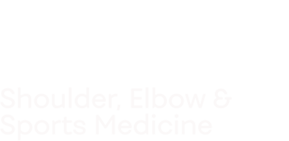

Microfracture

Goal:

Microfracture surgery aims to stimulate the growth of new articular cartilage cells by creating a new blood supply to the damaged area.

Process:

A sharp tool called a microfracture pick is used to make multiple holes in the joint surface, beneath the cartilage and within the bone. These activate a natural healing response—the perforations allow bone marrow with stem cells access to the cartilage injury that will help new cartilage to form.

Microfracture surgery can be done arthroscopically and is a procedure best suited for younger patients with smaller areas of cartilage damage.

Steps of the microfracture technique. Left: Damaged cartilage is removed. Center: Microfracture pick instrument is used to make perforations in thebone. Right: Healing response brings bone marrow cells to the defect and forms new cartilage.